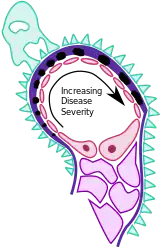

| Types | Stage 1 to 4[2] |

- On electron microscopy, subepithelial deposits that nestle against the glomerular basement membrane seems to be the cause of the thickening. Also, the podocytes lose their foot processes. As the disease progresses, the deposits will eventually be cleared, leaving cavities in the basement membrane. These cavities will later be filled with basement membrane-like material, and if the disease continues even further, the glomeruli will become sclerosed and finally hyalinized.